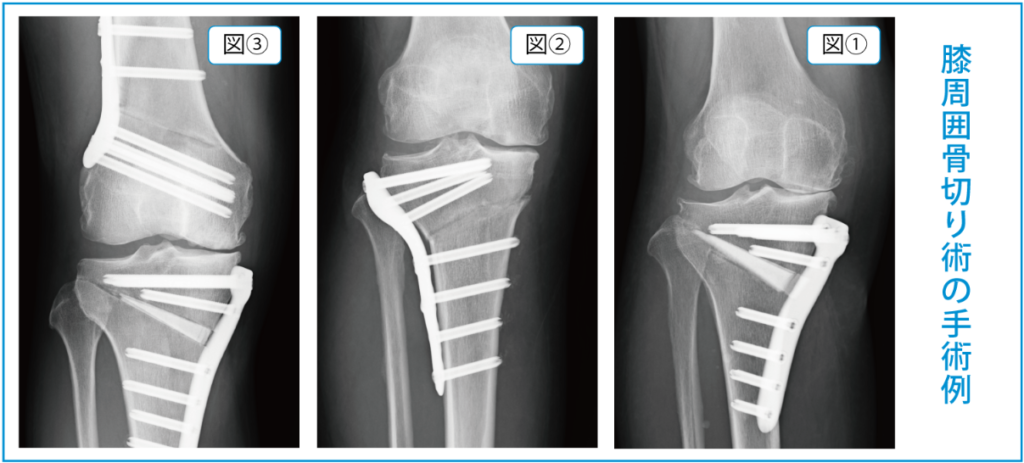

「膝周囲骨切り術」は大腿骨(太ももの骨)や脛骨(すねの骨)の膝に近い部分を切って向きを変えO脚を矯正する方法です。

この手術では、骨の変形の部位や程度、矯正する角度に応じて骨切りする部位などが変わってきます。一番多いのは内側開大式高位脛骨骨切り術といって脛骨の内側を骨切りし開いて人工骨を挿入する方法(図1)です。他にも外側閉鎖式高位脛骨骨切り術や遠位大腿骨骨切り術(図2)、また場合によってはそれらを組み合わせた大腿骨・脛骨両側骨切り術(図3)などもあります。